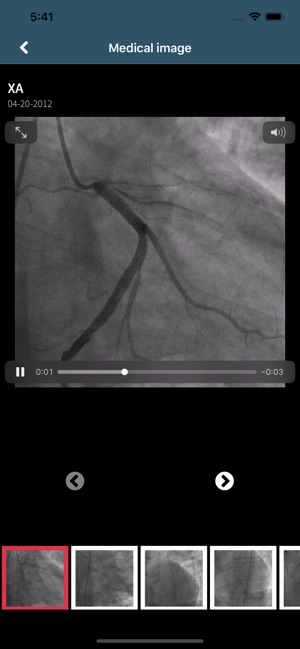

- Upload your MRIs, CT scans and other medical images securely and share them with your medical provider from your screen.